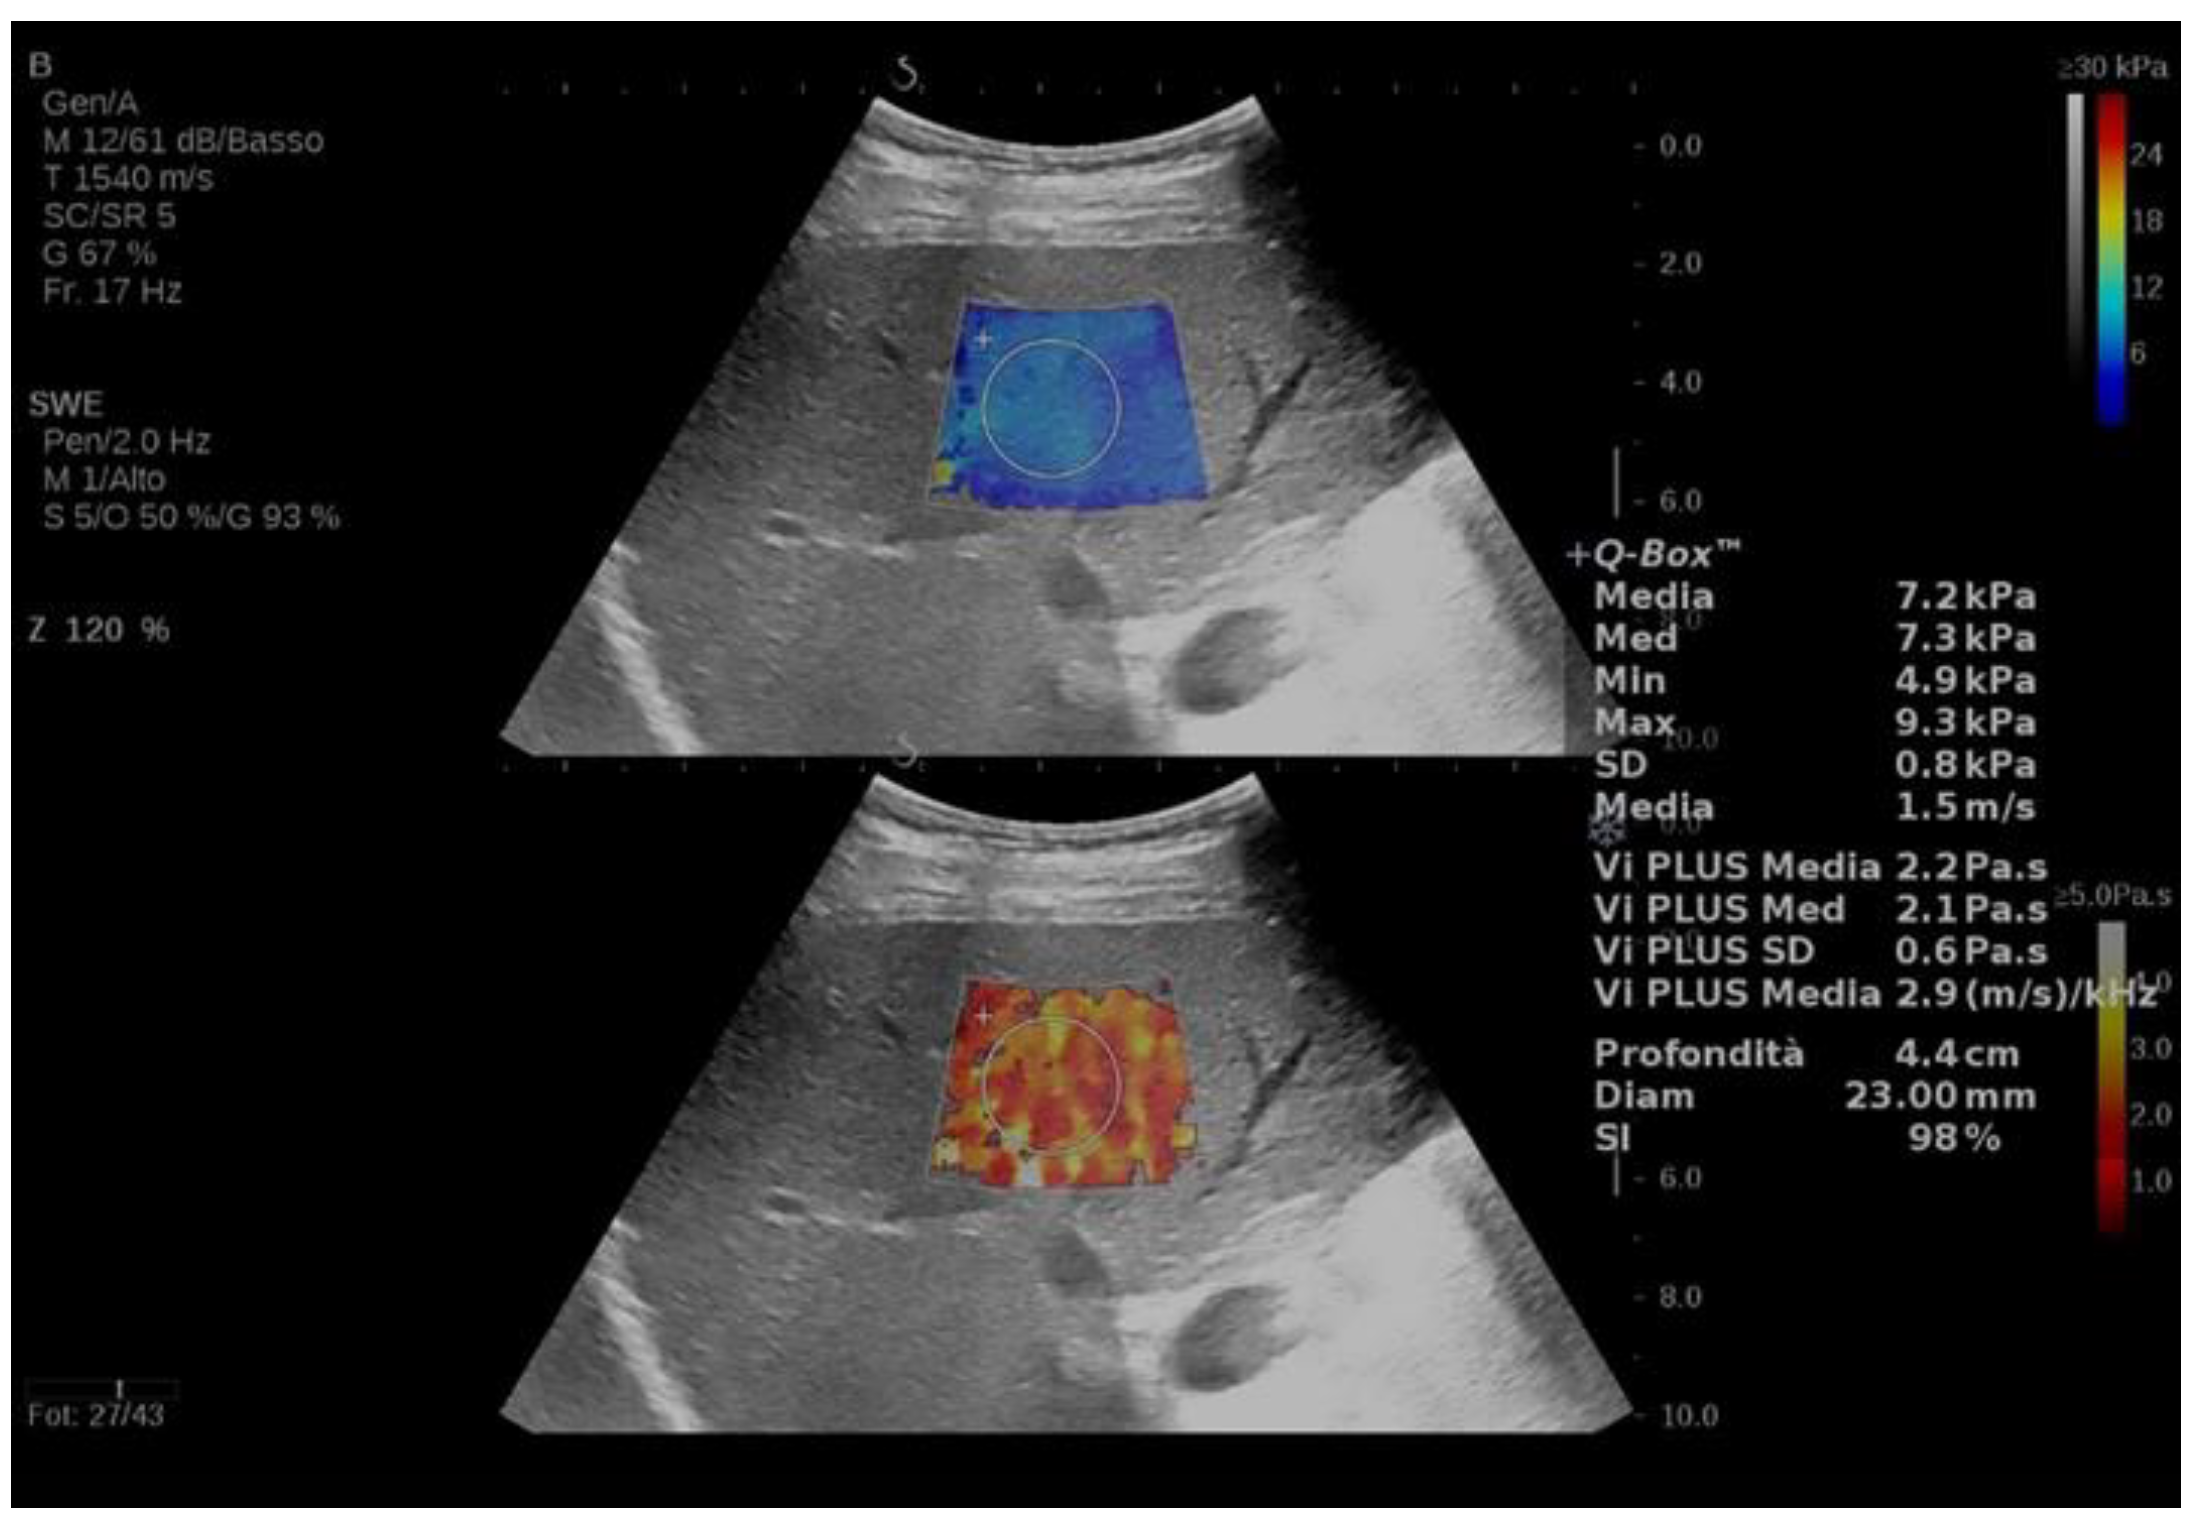

| Popa et al. (2021) [47] | Cross-sectional (204) | - | Patients undergoing liver US | Supersonic MACH 30 with Vi.Plus | Viscosity (Pa·s) | All patients: 1.8 (0.83) | BMI and liver stiffness measured with 2D shear wave elastography were independently associated with Vi.Plus. |